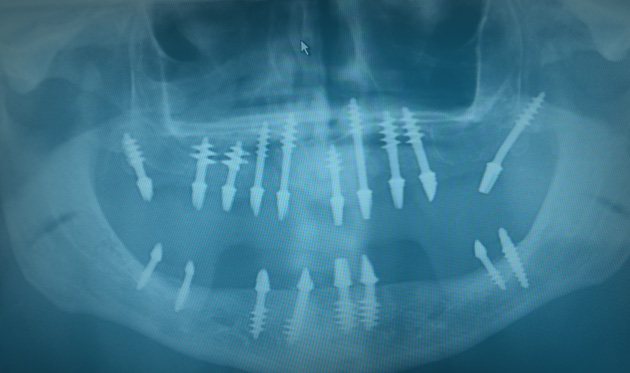

Low cost implants at Dental Relax Budapest A person can lose a tooth for any number of reasons: for some, it is a result of genetics, while...